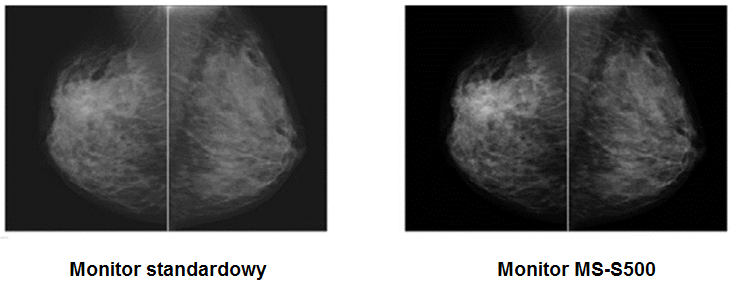

Zwiększona efektywność diagnostyczna

Monitor MS-S500 jest fabrycznie kalibrowany do jasności 1000 cd / m2, co czyni go najlepszym rozwiązaniem do ogladania obrazów piersi. Wysoka jasność ekranu monitora radykalnie zwiększa ilość widzianych odcieni szarości, dzięki czemu wykrywalność mikrozwapnień i guzów jest dużo większa.

Poprawa jakości diagnostycznej

Wysoki współczynnik kontrastu 2000:1 gwarantuje bardzo wyraźny obraz ułatwiając radiologom interpretację wyników i zwiększając wydajność pracy.